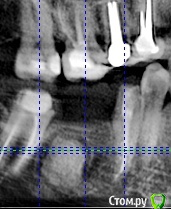

Тимур86 Опубликовано 5 ноября, 2019 Автор Поделиться Опубликовано 5 ноября, 2019 Ну вот на панораме вроде есть, а на срезах не сказать Ссылка на комментарий

Тимур86 Опубликовано 1 октября, 2020 Автор Поделиться Опубликовано 1 октября, 2020 Есть похожая ситуация! Но тут сложнее :глубже, и в непосредственной близости с нервом... У кого какие мысли? Ссылка на комментарий